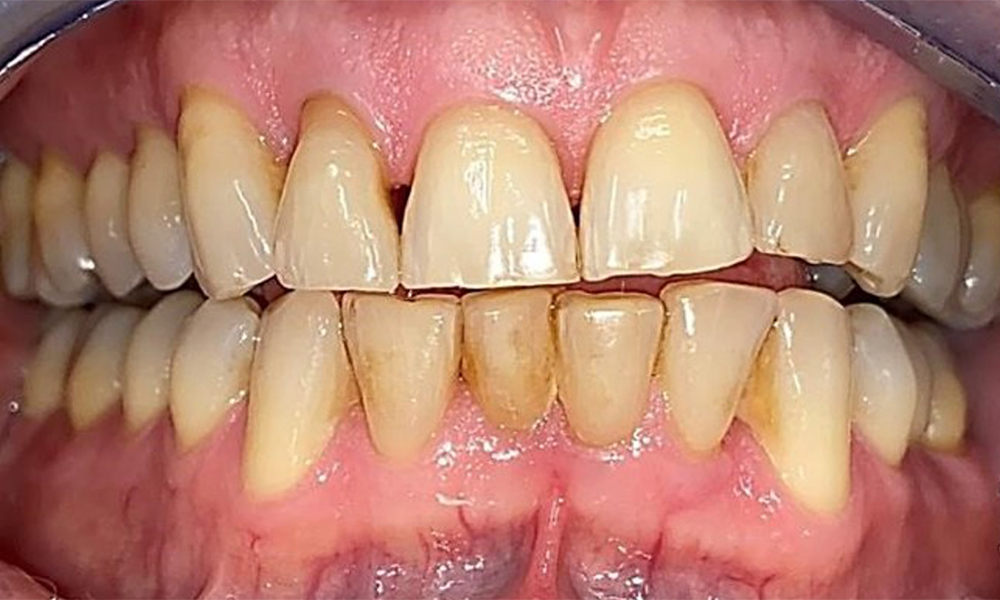

Зъбни резултати

Пациентът има пълно съзъбие с 28 зъба, което включва амалгамни и композитни пломби в областта на моларите и премоларите. На зъб 14 има видима клинична маргинална празнина. Зъб 27 има адекватна златна инкрустация. Налице са и генерализирани атриции и абразии. (фиг. 2, фиг. 3, фиг. 4, фиг. 5, фиг. 6)

Пародонтални резултати

Пациентът е с пародонтит II стадий, степен В (5). Клиничните дълбочини на сондиране от 1 до 3 mm са във физиологичния диапазон. Локализирани дълбочини на сондиране от 5 mm са наблюдавани медиопалатинално на 17 и 27. Налице са генерализирани рецесии от 1 до 3 mm с частична загуба на интердентални папили (фиг. 2, фиг. 3, фиг. 4)